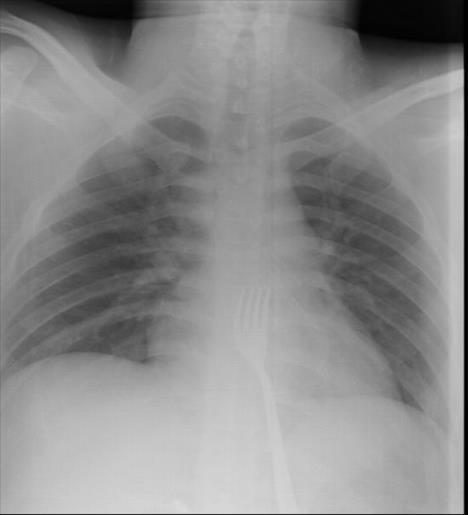

Na snimku je uočena metalna viljuška duga 15 centimetara, koju su lekari potom odstranili iz tela. Hirurg Mehmet Erikoglu je kako je sreća da je mladić viljušku progutao "naopačke" pa glatka strana drške nije napravila veća oštećenja pri prolasku kroz jednjak.

"Bilo je mnogo slučajeva da ljudi progutaju različite predmete, ali ovo je prvi put da smo se susreli sa slučajem da je neko progutao viljušku", kazao je Erikoglu.